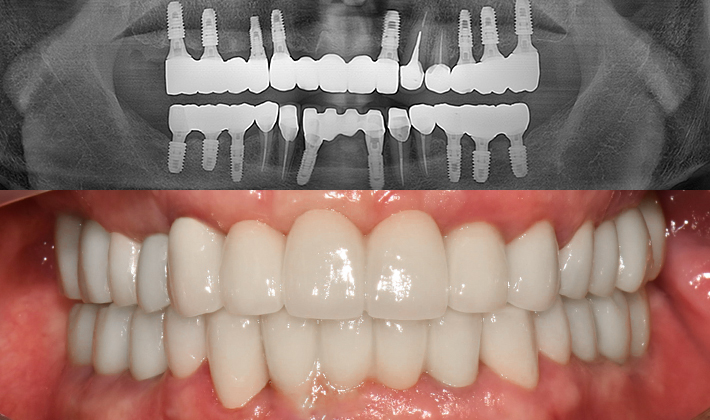

치과가 무서워 10년 동안 미뤄온 임플란트 수술 그 결과는?

2026.01.21